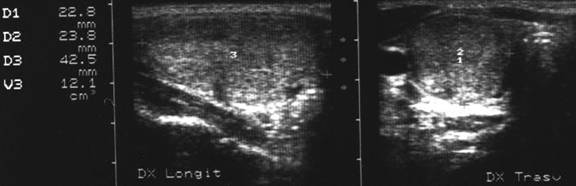

Femeie 25 ani. Nodul unic in lobul stang, contur net, hipoecogen, respecta parenchimul din jur, neomogen, de 18x23x36 mm (7,5 cc).

Citoaspiratia cu ac subtire: nodul adenomatos.

Examen histologic postoperator: adenom trabecular fetal.

Acelasi caz. La doppler color - vascularizatie interna, mai evidenta in powerdoppler.

Apexul lobului drept, proiectie longitudinala si trasversala.